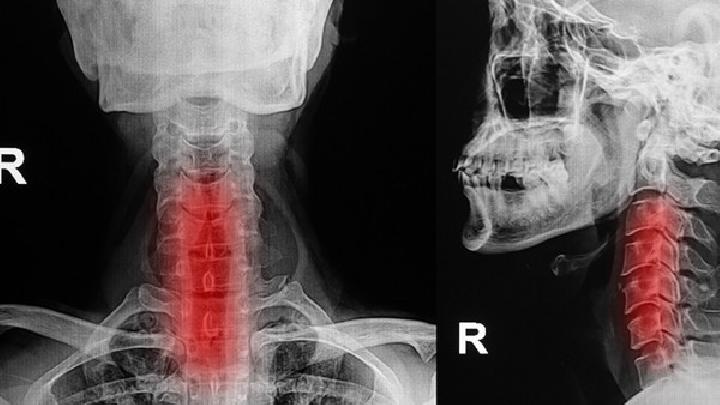

X线检查

X线检查可以查见心影大小及外形,这种检查能为心脏病的病因诊断提供比较重要的参考资料,根据心脏扩大的程度和动态改变也可间接反映心脏功能状态。如果患者有肺淤血,检查主要表现为肺门血管影增强,上肺血管影增多与下肺纹理密度相仿,甚至多与下肺。

由于肺动脉压力增高可见右下肺动脉增宽,进一步出现间质性肺水肿可使肺野模糊,KerleyB线是在肺野外侧清晰可见的水平线状影,是肺小叶间隔内积液的表现,是慢性肺淤血的特征性表现。